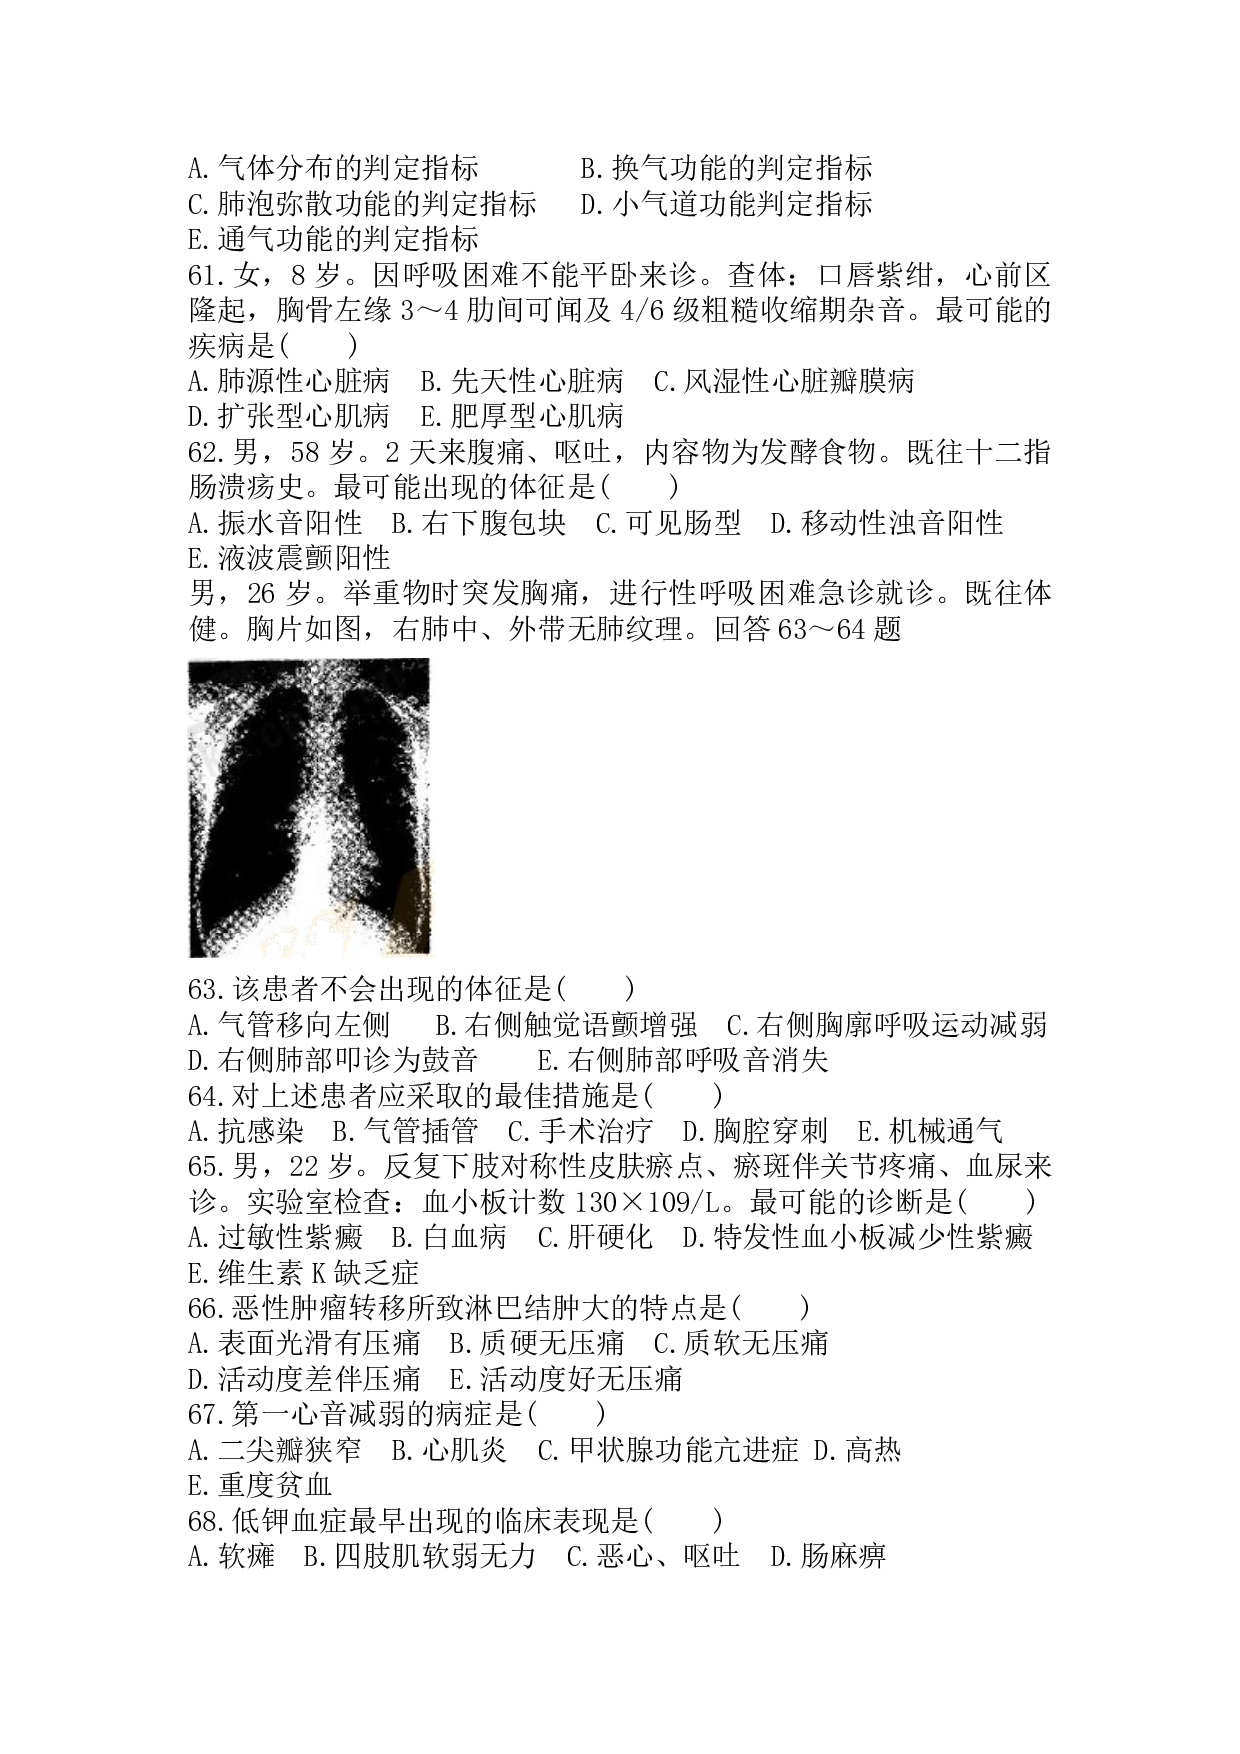

201 7 年成人高等学校招生全国统一考试专升本 医学综合 一 、 A 型题 : 1~ 84 小题 , 每小题 l.25 分 , 共 105 分 。 在每小题给出 的 A、 B、 C、 D、 E 五个选项中,请选出一项最符合题目要求的。 1. 骨的构造中含有丰富血管和神经的是 ( ) A. 骨密质 B. 骨膜 C. 骨松质 D. 红骨髓 E. 黄骨髓 2. 含有关节盘的关节是 ( ) A. 肩关节 B. 肘关节 C. 髋关节 D. 颞下颌关节 E. 踝关节 3. 咽鼓管的开口部位在 ( ) A. 扁桃体窝 B. 咽腔口部的侧壁 C. 咽腔喉部的侧壁 D. 梨状隐窝 E. 咽腔鼻部的侧壁 4. 肱二头肌的作用是 ( ) A. 使肱骨内收、内旋和前屈 B. 屈肘关节、屈肩关节和使前臂旋前 C. 伸肘关节,其长头伸和内收肩关节 D. 伸肘关节 .其长头伸和外展肩关节 E. 屈肘关节、屈肩关节和使前臂旋后 5. 肝下面右纵沟前部容纳的结构是 ( ) A. 下腔静脉 B. 胆囊 C. 肝圆韧带 D. 静脉韧带 E. 肝十二指肠韧带 6. 与阴道后穹相邻的结构是 ( ) A. 直肠子宫陷凹 B. 膀胱子宫陷凹 C. 直肠膀胱陷凹 D. 盲肠后隐窝 E. 膀胱上窝 7. 喉腔内易发生水肿的部位是 ( ) A. 喉口 B. 喉前庭 C. 喉室 D. 声门下腔 E. 喉中间腔 8. 肺下界的体表投影在腋中线相交于 ( ) A. 第 5 肋 B. 第 6 肋 C. 第 8 肋 D. 第 7 肋 E. 第 l0 肋 9. 膀胱三角的位置在 ( ) A. 膀胱尖内面 B. 膀胱体内面 C. 膀胱底内面 D. 膀胱颈内面 E. 膀胱前壁内面 10. 精囊腺的位置在 ( ) A. 阴囊内 B. 睾丸的后方 C. 膀胱底的后方 D. 前列腺的后方 E. 输精管末段的内侧 11. 走行通过腹股沟管的结构是 ( ) A. 骶子宫韧带 B. 子宫圆韧带 C. 子宫主韧带 D. 子宫阔韧带 E. 卵巢固有韧带 12. 子宫动脉在子宫颈外侧 2cm 处跨过输尿管的正确位置是 ( ) A. 后上方 B. 前方 C. 下方 D. 后方 E. 后下方 13. 下列不属于主动脉分部的是 ( ) A. 升主动脉 B. 头臂干 C. 主动脉弓 D. 胸主动脉 E. 腹主动脉 14. 下列属于锁骨下动脉分支的是 ( ) A. 甲状腺上动脉 B. 脑膜中动脉 C. 胸廓内动脉 D. 上颌动脉 E. 食管动脉 15. 下列属于肠系膜上动脉的分支是 ( ) A. 右结肠动脉 B. 左结肠动脉 C. 乙状结肠动脉 D. 直肠上动脉 E. 直肠下动脉 16. 肩关节外展困难可能损伤的神经是 ( ) A. 正中神经 B. 肌皮神经 C. 桡神经 D. 尺神经 E. 腋神经 17. 通过颈静脉孔的脑神经是 ( ) A. 面神经 B. 舌下神经 C. 副神经 D. 前庭蜗神经 E. 三叉神经 18. 舌下神经核属于的机能柱是 ( ) A.